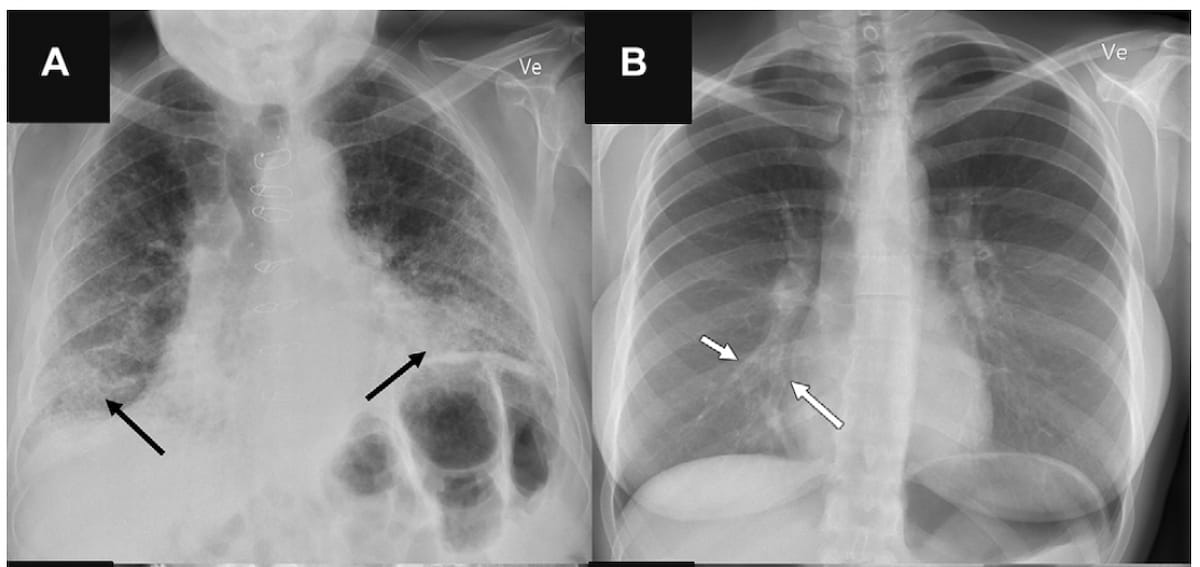

The research findings also revealed lower specificity rates of the AI tools when there were four or more findings on chest X-ray with ranges of 27 to 69 percent for airspace disease, 96 to 99 percent for pneumothorax and 65 to 92 percent for pleural effusion. While the AI tools had sensitivity rates ranging between 81 and 100 percent for larger findings on chest X-rays, the study authors noted lower sensitivity for vague airspace disease (33 to 61 percent) and small pneumothorax and pleural effusion (9 to 94 percent).

“Furthermore, we found that AI sensitivity generally was lower for smaller-sized target findings and that AI specificity generally was lower for anteroposterior chest radiographs and those with concurrent findings.”